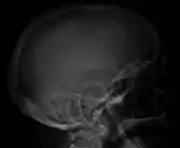

Skull X-ray showing multiple lucencies due to multiple myeloma

The diagnostic examination of a person with suspected multiple myeloma typically includes a skeletal survey. This is a series of X-rays of the skull, axial skeleton, and proximal long bones. Myeloma activity sometimes appears as "lytic lesions" (with local disappearance of normal bone due to resorption) or as "punched-out lesions" on the skull X-ray ("raindrop skull"). Lesions may also be sclerotic, which is seen as radiodense.[70] Overall, the radiodensity of myeloma is between −30 and 120 Hounsfield units (HU).[71] Magnetic resonance imaging is more sensitive than simple X-rays in the detection of lytic lesions, and may supersede a skeletal survey, especially when vertebral disease is suspected. Occasionally, a CT scan is performed to measure the size of soft-tissue plasmacytomas. Bone scans are typically not of any additional value in the workup of people with myeloma (no new bone formation; lytic lesions not well visualized on bone scan).

Bone pain affects almost 70% of people with multiple myeloma and is one of the most common symptoms.[2]: 653 [22] Myeloma bone pain usually involves the spine and ribs, and worsens with activity. Persistent, localized pain may indicate a pathological bone fracture. Involvement of the vertebrae may lead to spinal cord compression or kyphosis. Myeloma bone disease is due to the overexpression of receptor activator for nuclear factor κ B ligand (RANKL) by bone marrow stroma. RANKL activates osteoclasts, which resorb bone. The resultant bone lesions are lytic (cause breakdown) in nature, and are best seen in plain radiographs, which may show "punched-out" resorptive lesions (including the "raindrop" appearance of the skull on radiography). The breakdown of bone also leads to the release of calcium ions into the blood, leading to hypercalcemia and its associated symptoms.[23]